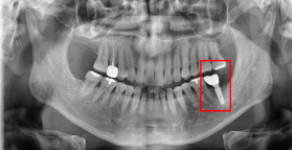

After(후)

사진을 보시면 임플란트가 안정적으로 자리 잡은 것을 확인해 보실 수 있습니다.

이분은 SCRP 크라운 보철물로 치료를 진행하였습니다.

SCRP 보철물은 사후관리가 용이하다는 장점을 가지고 있습니다. 우측 사진을 보시면 치료받은 치아에 동그라미를 확인해 보실 수 있는데요. 이게 작은 구멍입니다.

이 구멍을 통해 나사 조임을 조절하여 언제든지 보철물이 탈부착이 가능하기에, 보철물을 위생적으로 관리할 수 있습니다.

즉, 임플란트 후 잇몸질환, 임플란트후붓기 등 문제가 발생하였을 때, 치과를 방문하셔서 쉽게 치료가 가능하다는 장점이 있습니다.